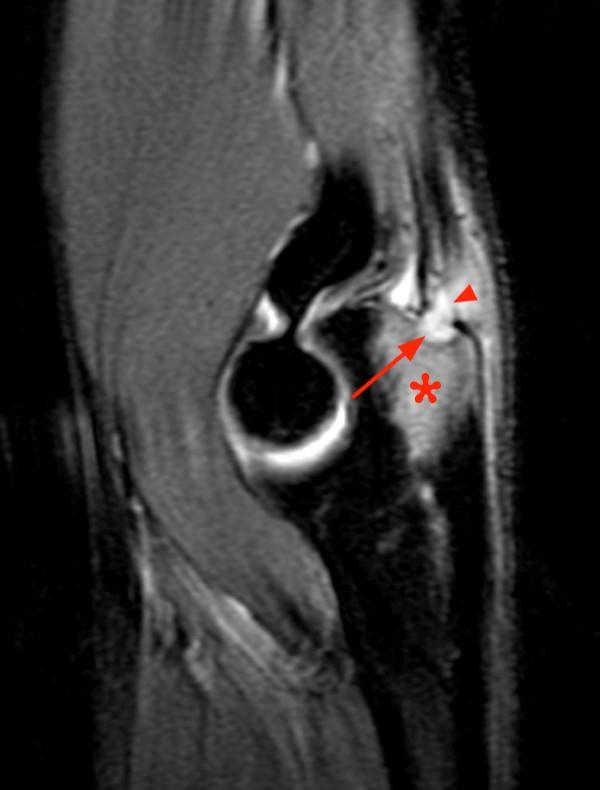

From www.pinterest.com

A Brodie abscess refers to an abscess related to focus of chronic Can An Abscess Cause Osteomyelitis This is known as an abscess. What are the symptoms of osteomyelitis? Bone infections can cause pockets of pus that break through your skin. Osteomyelitis is inflammation of the bone caused by an infecting organism. Infection may expand through the bone cortex and spread under the periosteum, with formation of subcutaneous abscesses that may drain spontaneously through the skin. Although. Can An Abscess Cause Osteomyelitis.

From radiopaedia.org

Chronic osteomyelitis with Brodie abscess Image Can An Abscess Cause Osteomyelitis Osteomyelitis is an inflammatory condition involving the medullary cavity of bone. Infection may expand through the bone cortex and spread under the periosteum, with formation of subcutaneous abscesses that may drain spontaneously through the skin. Bone infections can cause pockets of pus that break through your skin. It begins as a bacterial infection and can cause significant bony. Treatment to. Can An Abscess Cause Osteomyelitis.

Brodie abscess chronic osteomyelitis Image Can An Abscess Cause Osteomyelitis Bone infections can cause pockets of pus that break through your skin. Infection may expand through the bone cortex and spread under the periosteum, with formation of subcutaneous abscesses that may drain spontaneously through the skin. What are the symptoms of osteomyelitis? If untreated, osteomyelitis can lead to blood poisoning (sepsis) and/or an abscess in the bone. It begins as. Can An Abscess Cause Osteomyelitis.

Chronic osteomyelitis with Brodie abscess Image Can An Abscess Cause Osteomyelitis Infection may expand through the bone cortex and spread under the periosteum, with formation of subcutaneous abscesses that may drain spontaneously through the skin. Bone infections can cause pockets of pus that break through your skin. Treatment to drain these abscesses may slightly increase your risk of skin cancer. Osteomyelitis is a serious infection of the bone that can be. Can An Abscess Cause Osteomyelitis.